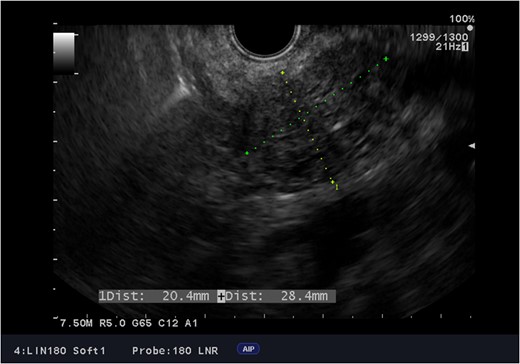

Endoscopic ultrasound images of the adenocarcinoma of the head of the pancreas.

Due to LVAD streaking artifact on CT, pre-operative good quality imaging of the pancreas was only possible with endoscopic ultrasound.